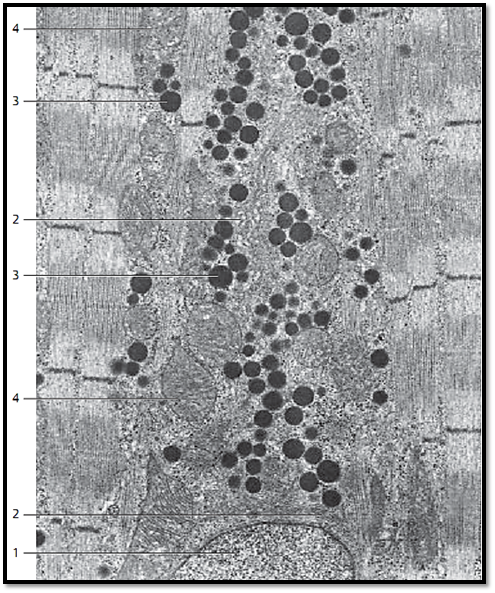

Cardiac Muscle—Myocardium—Myoendocrine Cells from the Right Atrium

Myoendocrine cells have a typical morphology. The endocrine secretor y apparatus, for example, exists only in the Golgi region in or close to the sarcoplasmic cones 1 , which is rich in sarcoplasm and poor in myofibrils. Golgi complexes 2 can be located either close to or further away from the nucleus. Secretor y granules 3 occur mainly in the Golgi regions, but sporadically there are also secretor y granules in the rest of the cytoplasm. They often form lines of vesicles in the space between fibrils. The secretory granules contain antigens, which react with antibody to cardiodilatin.

Note the crista-type mitochondria 4 . Left and right in the figure are typical striate d myofibrils.

1 Nucleus of a myoendocrine cell

2 Golgi complex (Golgi apparatus)

3 Secretor y granules

4 Mitochondria

Electron microscopy; magnification: × 11 000